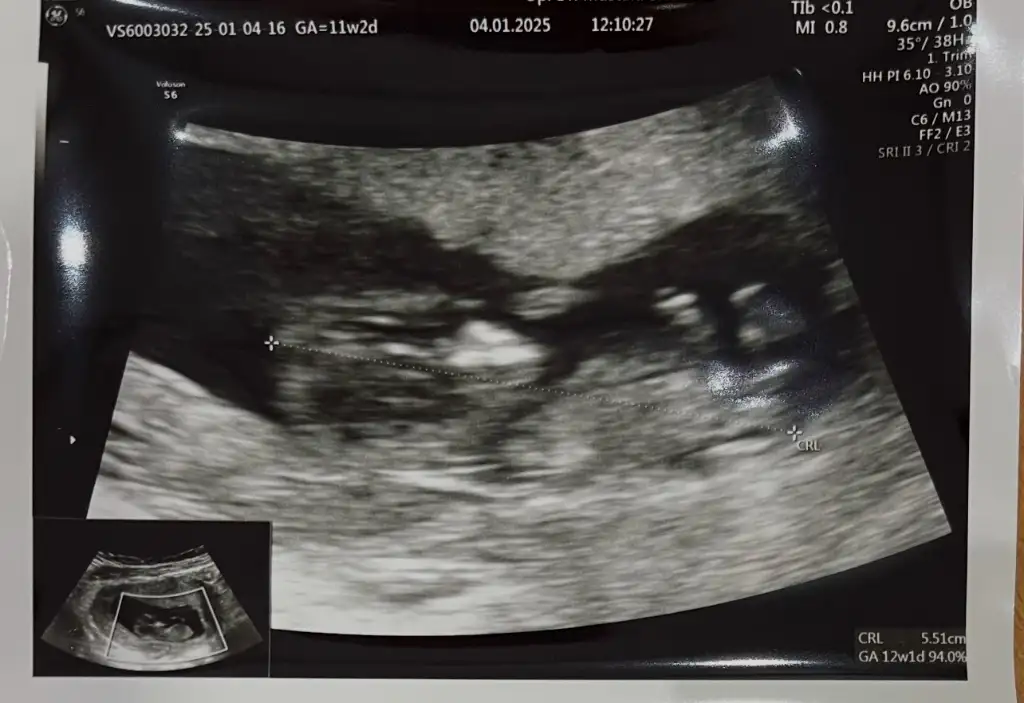

Merhaba 11+2 haftalık ultrason cinsiyet tahmini yapabilir misiniz acaba ?

Eki Görüntüle 3531429

Bence erkek

Erkek bence, çıkıntıdan ziyade vajinayı anımsatan 3 çizgi de görünmüyor. Tok tok duruyor bacak arasısağlıcakla gelsin inşallah

Erkek gibi benzettim ama tabii emin değilim canım